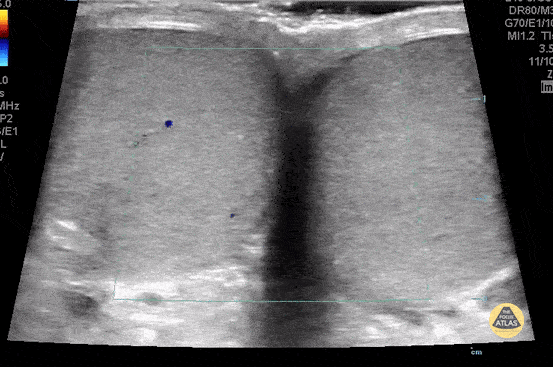

Normal testicle buddy view with color. The buddy view is the best place to start when doing as testicular ultrasound to compare the echogenicity, size, blood flow and position of the testicles. Contributor: Paul Khalil, MD Nicklaus Children's Hospital @khalil3paul